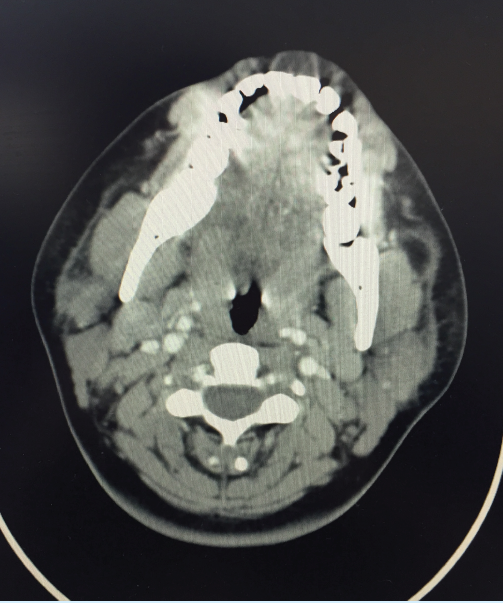

tumor

Mariam Fahim, DO; Judith Oh Leonor, OMS-IV

A male born via normal spontaneous vaginal delivery with unremarkable prenatal labs was noted to have a 1-cm lesion near the vertex of the skull.